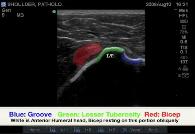

Biceps Tendon dislocation